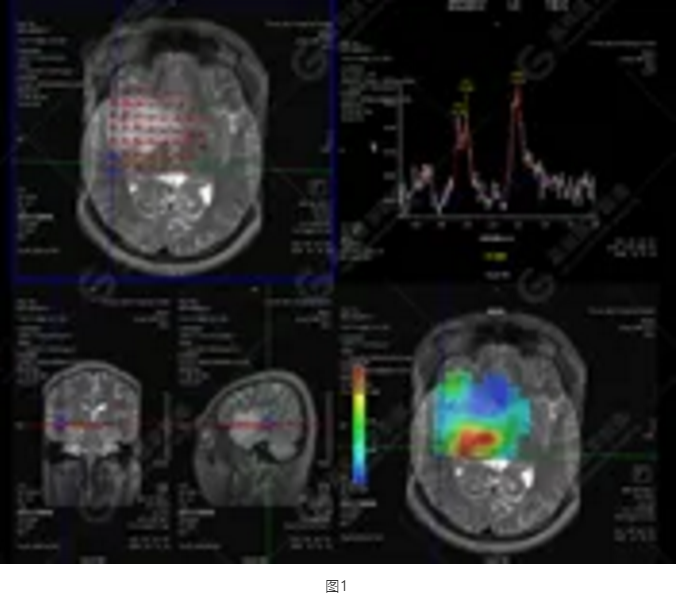

圖1為多體素MRS檢查,感興趣區(qū)為正常腦組織的MRS表現(xiàn)。圖2為單體素MRS,右側(cè)顳葉病灶內(nèi)NAA峰明顯下降,Cho峰明顯升高,NAA/Cr值為0.1,Cho/Cr值為3.64。